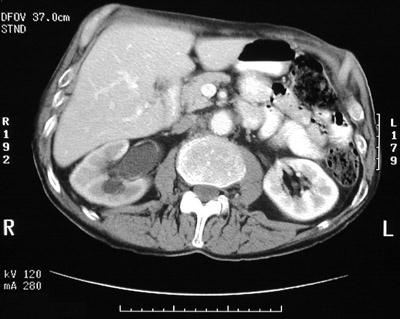

| This abdominal CT scan with contrast demonstrates right hydronephrosis as a consequence of ureteral obstruction. The pelvis and proximal ureter are dilated. The view below was obtained after placement of a stent from bladder to ureter to provide drainage. The stent is bright. |